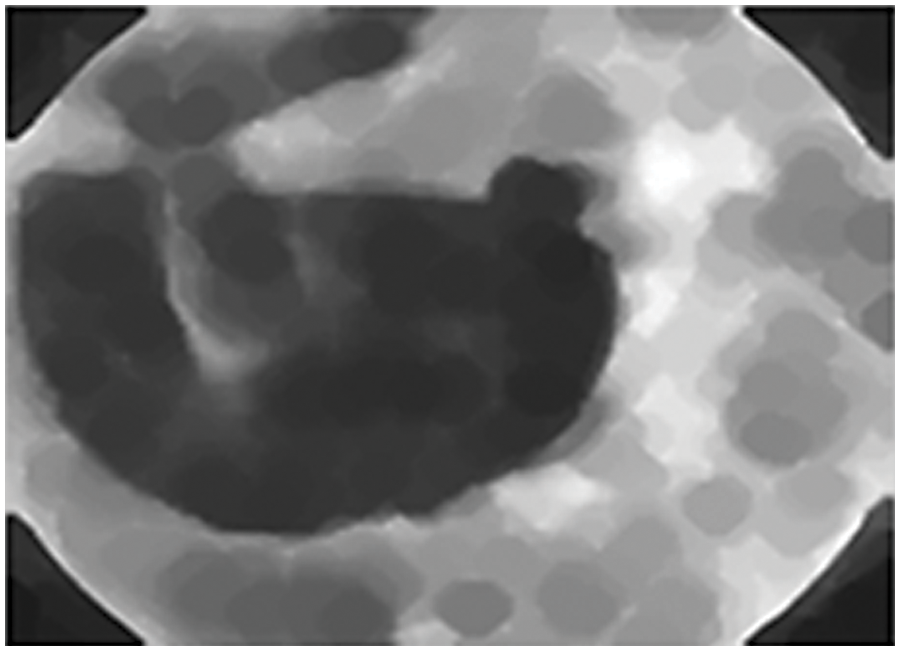

Through fundus imaging [12], the data set is taken and earlier days segmentation is done by optic disc segmentation method, and robust vessel segmentation [13]. These methods only segment [14] the specified dilemmas such as glaucoma, but our proposed segmentation uses vessel extraction [15] and a Graph cut segmentation algorithm. Through this graph theory, input fundus images are graph cut segmented which is shown in Fig. 1, it detects a specified portion of DR, through the line that is to be drawn in the fundus image. The background and the foreground superpixel differentiation make the segmentation easier by the Graph Cut algorithm, the MATLAB® toolstrip is an automatic segmenter that accesses the fundus image and segments automatically by the proposed algorithm.

Figure 1: Graph cut segmented fundus image

Graph cut segmentation is a recurrent technique for extracting the specific areas of an image that represent diabetic retinopathy lesions and the segmented image using the graph cut technique is shown in Fig. 6. When graph cut segmentation is applied, each pixel is regarded as a node. The nodes are then connected by edges. Weights are computed and distributed between pixels, as well as between the source and the sink. We classified the pixels 1 and 0 as foreground and background respectively and then identified them using the energy function. Images can be segmented at a reasonable cost by partitioning graphs in the same way. During graph theory of segmentation, the same featured pixels will be in the same segment, whereas dissimilar featured pixels will be in separate segments. Cutting a graph into disjoint subsets is called graph cutting. In a superpixel graph cut segmentation method fundus image is segmented into multiple sets of the segmented image as pixels or superpixels. It represents the contrasted fundus image. Superpixels align the segmented image with better edges and patches. In image segmentation, superpixels may take more image information than the pixels.